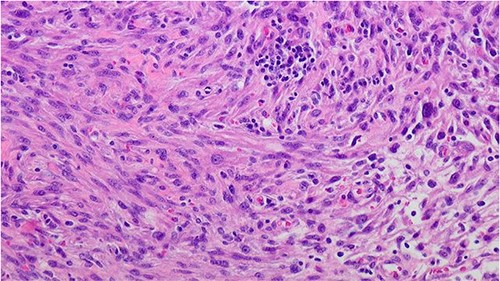

In contrast to the prior biopsies, the resection specimen revealed the tumor harbored areas with marked nuclear atypia, high cellularity, mitoses, and necrosis. A diagnosis of poorly differentiated leiomyosarcoma was rendered, with margins free of tumor (closest was 2 mm) (Fig. 3). The patient had an uneventful recovery. He reported complete resolution of his obstructive symptoms 1 month after the procedure. Given his recent diagnosis of high-grade cancer, adjuvant conventional fractionation radiotherapy targeting the postoperative bed without any elective nodal coverage was undertaken. Two months after radiotherapy, he reported having a normal urinary stream, good erections with penetration and forward ejaculation. He has now been on follow-up for the past 24 months with six monthly CT scans with no evidence of recurrence (Fig 4).

Prostate leiomyosarcoma (high grade/poorly differentiated) 200×: the tumor shows marked nuclear atypia and pleomorphic nuclei.